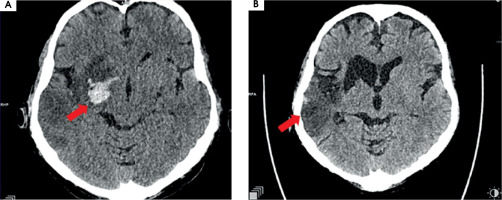

Twelve hours after admission to ICCU, in the presence of medical staff, the patient experienced symptoms of the stroke such as dysarthria, drooping of the corner of the mouth at the left side, and severe weakness of the left upper and lower limbs. The computed tomography (CT), which was performed immediately, showed that a high attenuation of the right middle cerebral artery (RMCA) was present (Figure IA). Angio-CT of cerebral arteries confirmed the occlusion of RMCA at segment M1/M2 about 6.5 mm from the origin of RMCA (Figure IB). The VRT (volume rendering technique) reconstruction of cerebral arteries was performed based on angio-CT (Figure IC).

Figure I

A) Computed tomography without contrast – hyperdense right middle cerebral artery (RMCA). B) Angio-CT – occlusion of RMCA in M1/2 segment. C) VRT (volume rendering technique). Arrows show pathological lesions